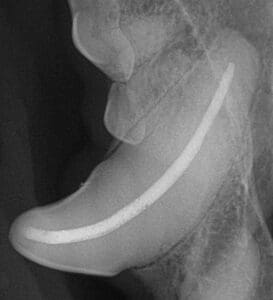

Root canal therapy involves the removal of inflamed or infected pulp inside a tooth, followed by cleaning and disinfection of the inside of the tooth. The tooth is filled with an inert material called Gutta Percha, which resembles rubber and is actually derived from the sap of the Palaquium tree. Finally, the access opening into the pulp chamber is filled with a restorative composite material, then sealed.